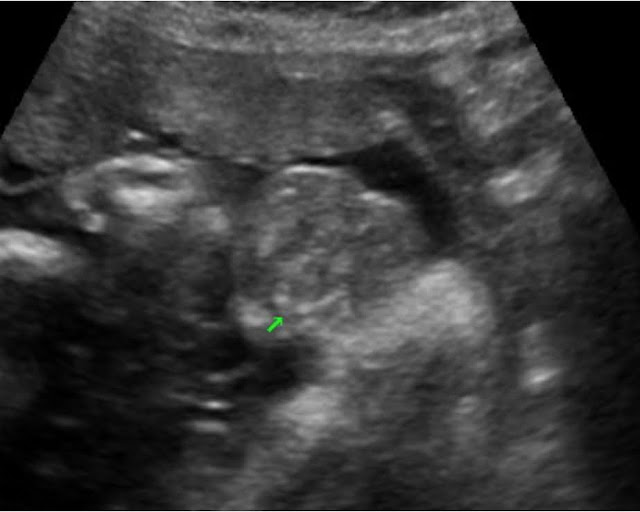

下半場由台兒診所周昱青醫師介紹肛門閉鎖 (Anal Atresia),肛門括約肌由三種肌肉形成perianal muscular complex (PAMC),分別為Internal sphincter, External sphincter, Puborectalis muscle,直腸和肛門的分界以提肛肌(Levator Ani muscle)做界線,無肛症 (imperforate anus)分為低位和高位,低位無肛會有完整的PAMC,高位無肛則可能缺乏PAMC或只剩一點點Internal sphincter,產前診斷相當困難,在2006年統計的產前診斷率約為16%。很少會單獨發生,約有85%會合併其他異常。肛門的超音波影像會看到如標靶(target sign)的影像,外圈低回音,內圈高回音(圖五),切面的標準不能看見骨盆的任何骨頭或股骨頭,如有看到上述的骨頭,表示切面切在胎兒較頭端的地方,為錯誤的切面;另一可能混淆的是會陰體(perineal body),在超音波下也會呈現高回音,但不會有外圈的低回音(圖六)。

圖五、Target sign(台兒診所提供)

圖六、會陰體(虛箭頭)和肛門(實箭頭)(台兒診所提供)